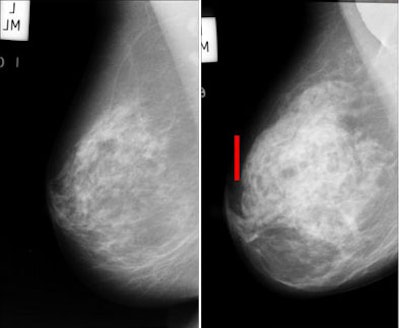

![]() |

| Architectural distortion in breast tissue (seen in mammographic breast image at right) is a potential indication of malignancy that is often missed by radiologists and CAD systems alike. The distortions can be difficult to appreciate even in the enlarged view (bottom). Images courtesy of Rangaraj Rangayyan, Ph.D. |